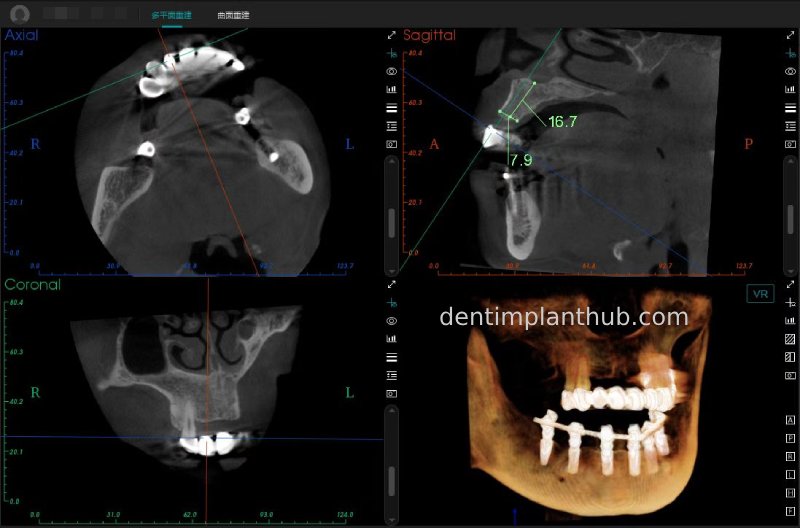

A review of the CBCT on 6/10/23 was more promising and a surgical plan was subsequently drawn up.

46

44

42

32

34

36

General schematic of the surgical programme

Detailed list of implant types and composite abutments to be prepared.

46 tooth position, implant model number 4810, RC series straight composite abutment;

44 tooth position, implant model number 4110, RC series straight composite abutment;

42 tooth position, implant model number 4110, RC series straight composite abutment; alternate implant model number 3310, alternate NC series straight composite abutment;

32 tooth position, implant model number 4110, RC series straight composite abutment; alternate implant model number 3310,. Alternate NC Series Straight Composite Abutment;

34 Dental Position, Implant Model No. 4110, RC Series Straight Composite Abutment;

36 Dental Position, Implant Model No. 4808, RC Series Straight Composite Abutment;